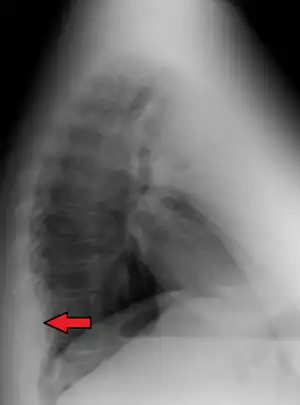

| Mediastinal lipomatosis | |